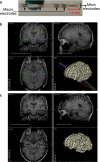

Recordings from individual neurons in patients who are implanted with depth electrodes for clinical reasons have opened the possibility to narrow down the gap between neurophysiological studies in animals and non-invasive (e.g. functional magnetic resonance imaging, electroencephalogram, magnetoencephalography) investigations in humans. Here we provide a description of the main procedures for electrode implantation and recordings, the experimental paradigms used and the main steps for processing the data. We also present key characteristics of the so-called 'concept cells', neurons in the human medial temporal lobe with selective and invariant responses that represent the meaning of the stimulus, and discuss their proposed role in declarative memory. Finally, we present novel results dealing with the stability of the representation given by these neurons, by studying the effect of stimulus repetition in the strength of the responses. In particular, we show that, after an initial decay, the response strength reaches an asymptotic value after approximately 15 presentations that remains above baseline for the whole duration of the experiment.